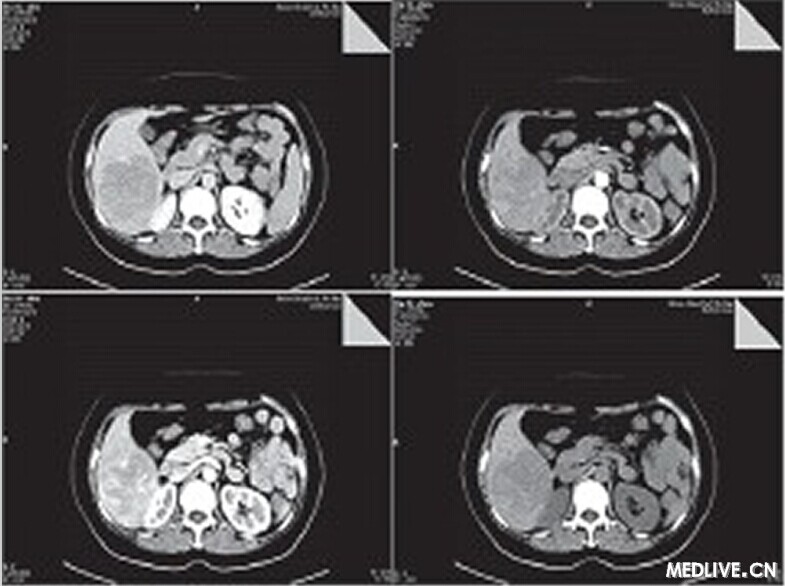

CT檢查平掃示肝右葉見6.6 cm×7.7 cm×8.8 cm塊影,CT值約為49 HU,病變內下緣與右腎上極分界欠清。動態增強掃描動脈期病變內見腫瘤血管影,延遲期呈相對低密度影,三期CT值分別為55.3 HU、85.8 HU、67.5 HU,腹膜后未見腫大淋巴結(如圖1所示)。結論:肝右后葉占位,肝癌可能性大,腹腔積液。

圖1 CT平掃

肝AML的CT影像學差異較大,主要取決于腫瘤內脂肪的含量及異常血管所占的比例,典型病例腫瘤內存在脂肪影時,CT值往往為負值。診斷肝AML不難,但部分肝AML在影像學上因缺乏脂肪而無特征性表現,容易誤診。本病例起初診斷為肝癌,因其較符合肝癌的CT影像學特點:在增強掃描時,表現為“快進快出”,動脈期明顯強化,可以看到多數細條彎曲強化的供血動脈及腫瘤實質區強化影,于門脈期雖然病灶實質部分仍有強化但病灶內動脈供血血管消失,于延時期病灶強化程度降低呈低密度影。

肝AML的CT影像學差異較大,主要取決于腫瘤內脂肪的含量及異常血管所占的比例,典型病例腫瘤內存在脂肪影時,CT值往往為負值,診斷肝AML不難。但部分肝AML在影像學上因缺乏脂肪而無特征性表現,容易誤診。如本病例腫瘤內缺少典型脂肪及平滑肌成分,形態上較為單一,影像學缺乏典型的血管平滑肌脂肪瘤特征,從而誤診為肝癌,值得引起臨床、影像科以及病理科醫生的注意。